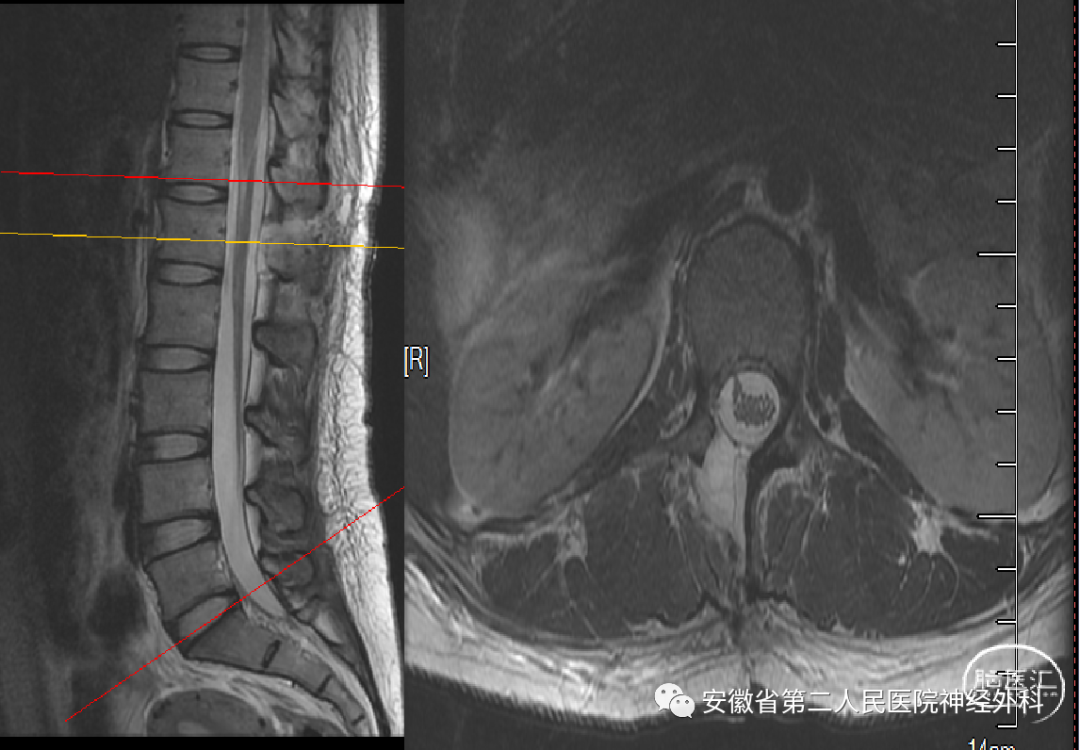

T1水平椎管内髓外硬膜下占位

患者约1年前无明显诱因下出现腰部疼痛,开始未予以重视,休息后无明显缓解,后期逐渐出现左侧腰臀及大腿外侧疼痛,且症状逐渐加重,频次逐渐增多,此次就诊我科门诊后安排住院。

术前CT

术前MRI